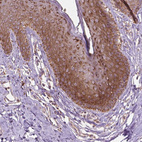

Immunohistochemical staining of human skin shows strong cytoplasmic granular positivity in squamous epithelial cells.